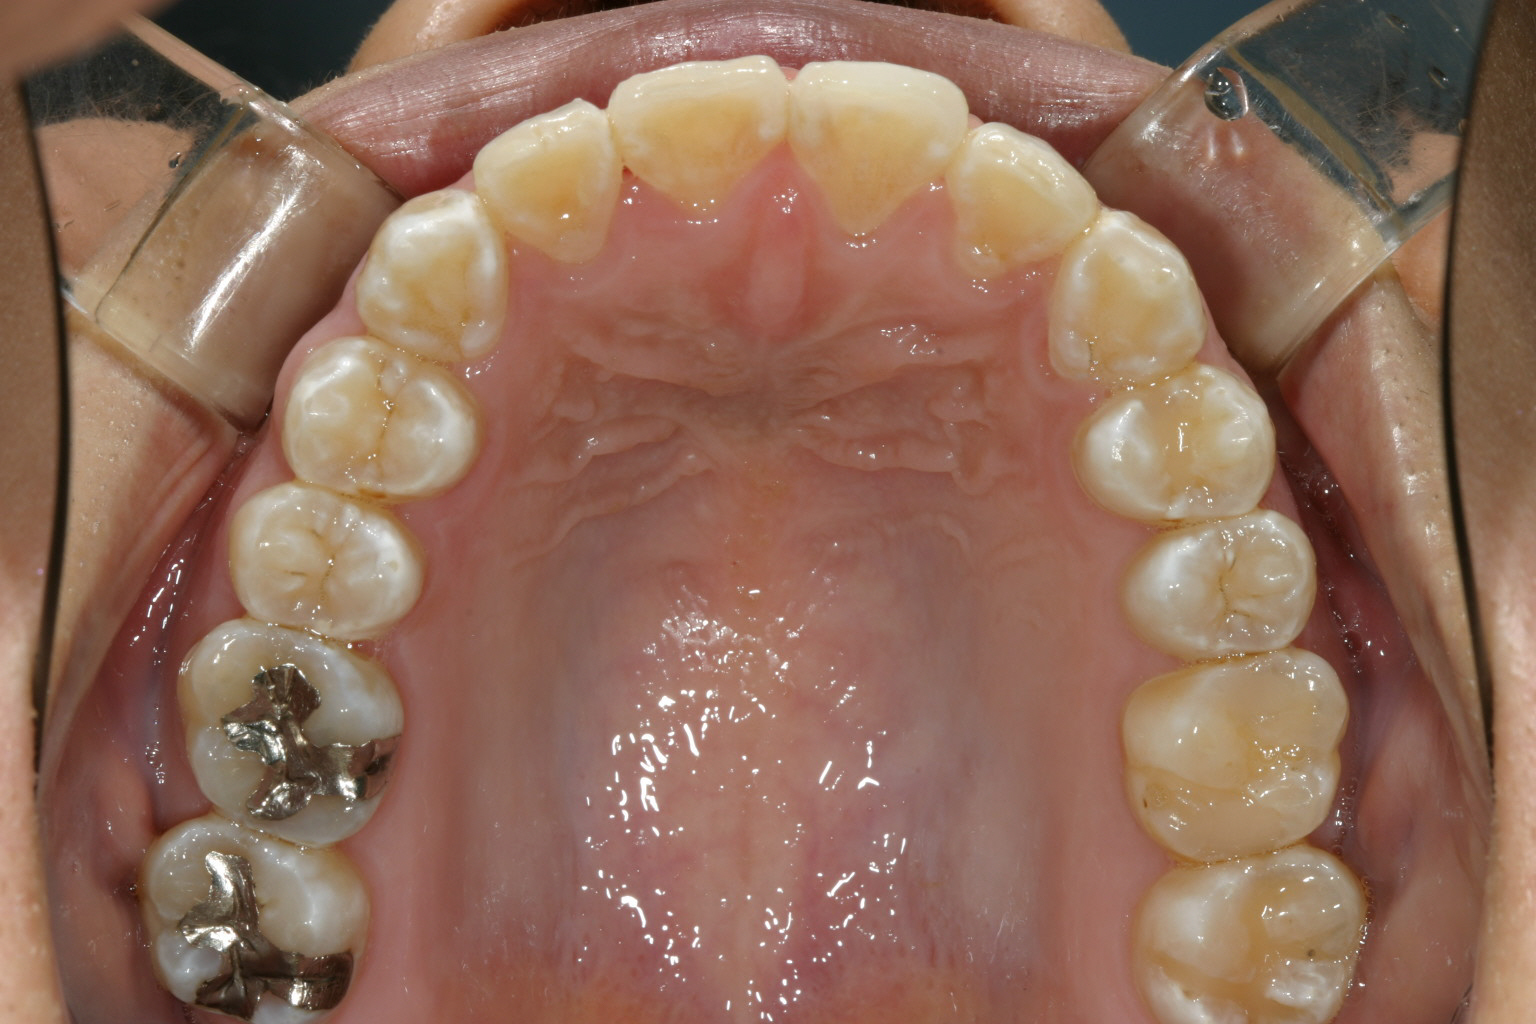

僅か半年でこんなに綺麗に改善しました。

下顎もバッチリ改善しています・

オーバージェットも出来ています。